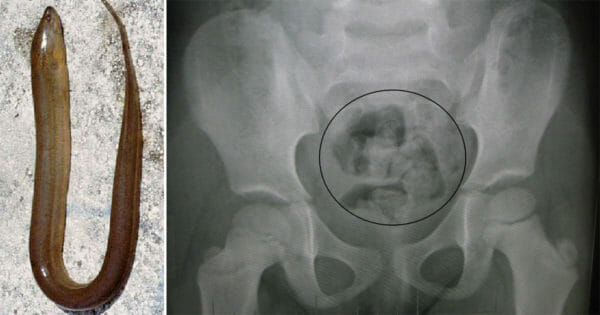

Desperat man kör upp 48 cm lång ål i ändtarmen – för att bota sin förstoppning

Människors galenskaper har man nästan slutat förvånas av nu för tiden, folk verkar kunna göra lite vad som helst. Vi på Humorbibeln har tidigare rapporterat om en man som körde upp en flaska i sitt ...